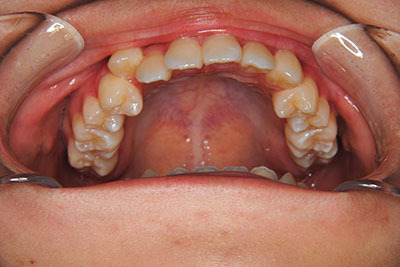

小学生高学年や中高生で矯正治療を考えている方へ

歯が乳歯から永久歯に生え変わった小学生高学年や、中高生でも矯正治療に手遅れということは全くありません。

成長中の顎の骨を矯正できたり、この時期の矯正はおとなになってから矯正治療を始めるよりも短期間で済むことがほとんどです。当院だとおおよそ1年で動的治療(マルチブラケット装置をつける期間)が終わることが多いです。